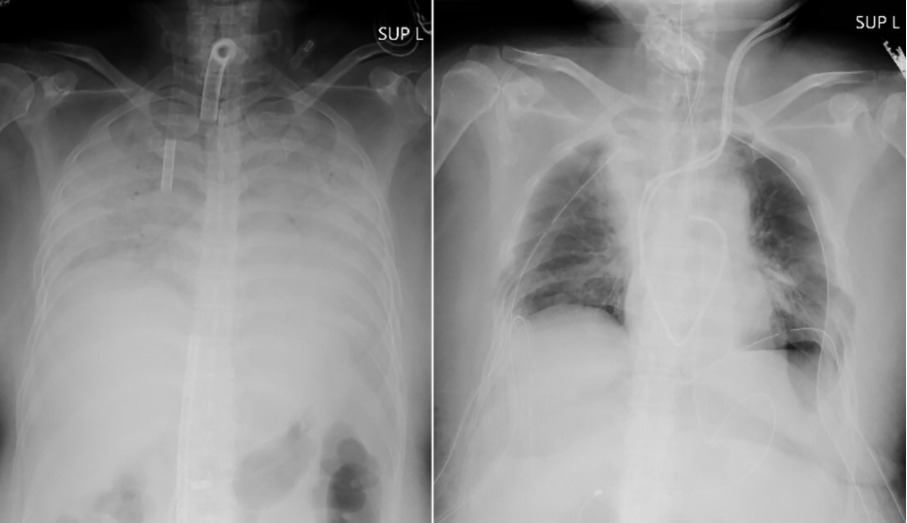

据悉,该女子在去年年底感染了COVID-19,呼吸困难,病情迅速加重。由于她的肺部严重受损,她在另一家医院接受人工肺生命支持机器的治疗长达3个多月。